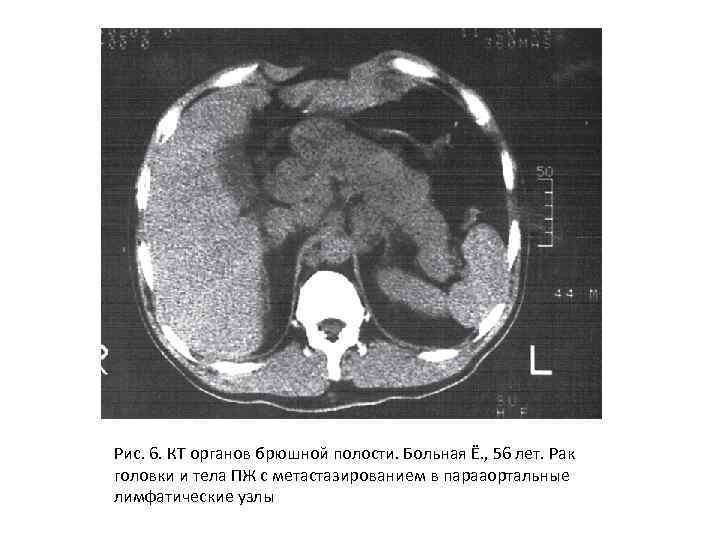

Компьютерная томография Наиболее характерными признаками рака поджелудочной железы при КТисследовании являлись деформация контуров и увеличение размеров органа, что зарегистрировано в 68, 9 % случаев, при этом в большинстве наблюдений увеличение размеров железы коррелировало с интрапаренхиматозным расположением опухолевого узла.

Рис. 6. КТ органов брюшной полости. Больная Ё. , 56 лет. Рак головки и тела ПЖ с метастазированием в парааортальные лимфатические узлы